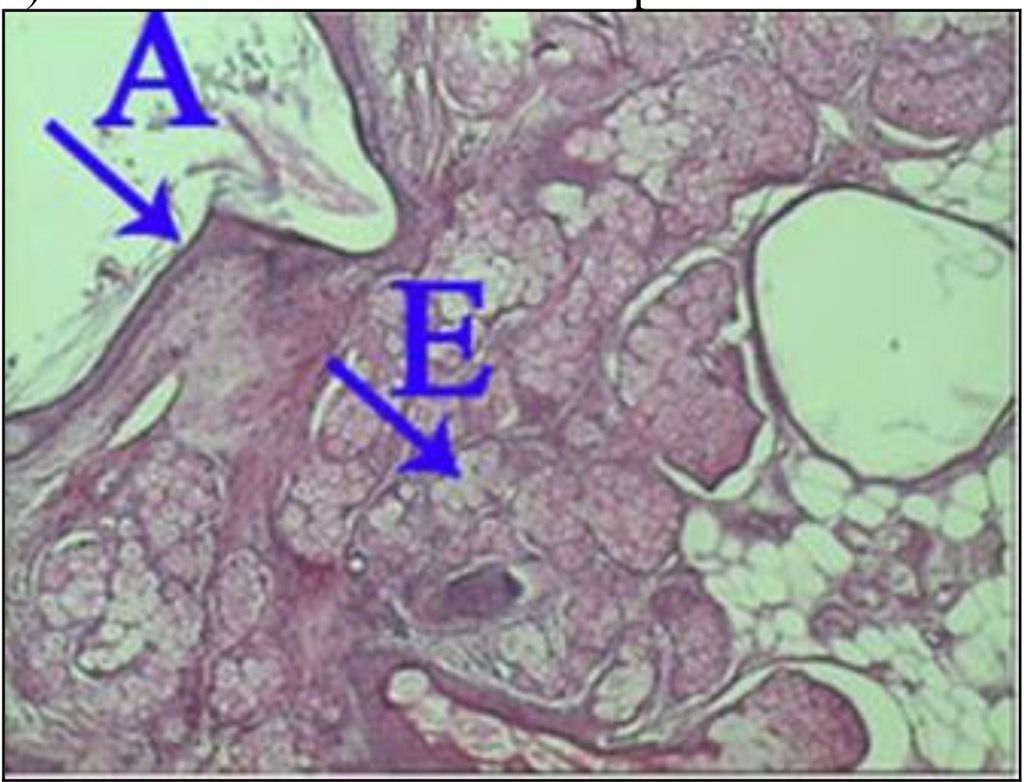

What is the correct answer at point A?

• - épithélium exocervical normal

• - membrane basale

• - cellules anormales

• - épithélium dysplasique sévère

• - massifs carcinomateux

What is the correct answer at point E?